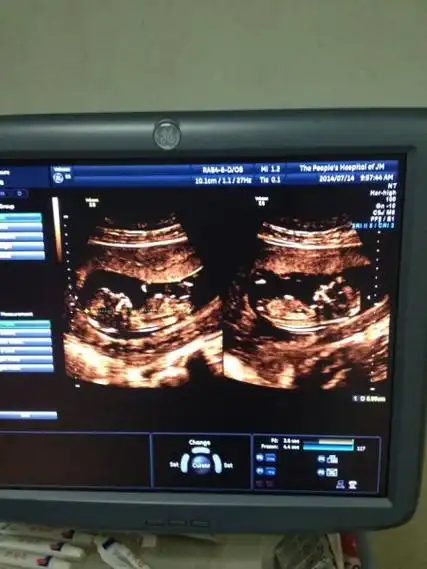

孕12周b超